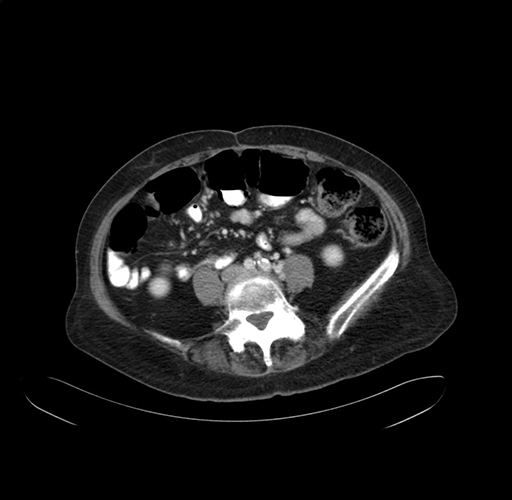

Pre-Chemo: Axial Venous

Axial Venous